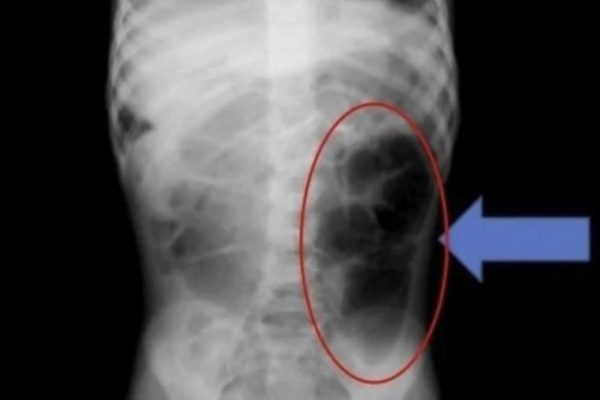

Hairball Found in 6-Year-Old Girl’s Stomach

Unusual Medical Case: Hairball Found in a Young Girl’s Stomach A recent medical case has raised concerns among healthcare professionals after a hairball was discovered in the stomach of a 6-year-old girl. The incident highlights the rare but serious condition known as “Rapunzel syndrome,” where individuals swallow large amounts of hair, leading to potential gastrointestinal…